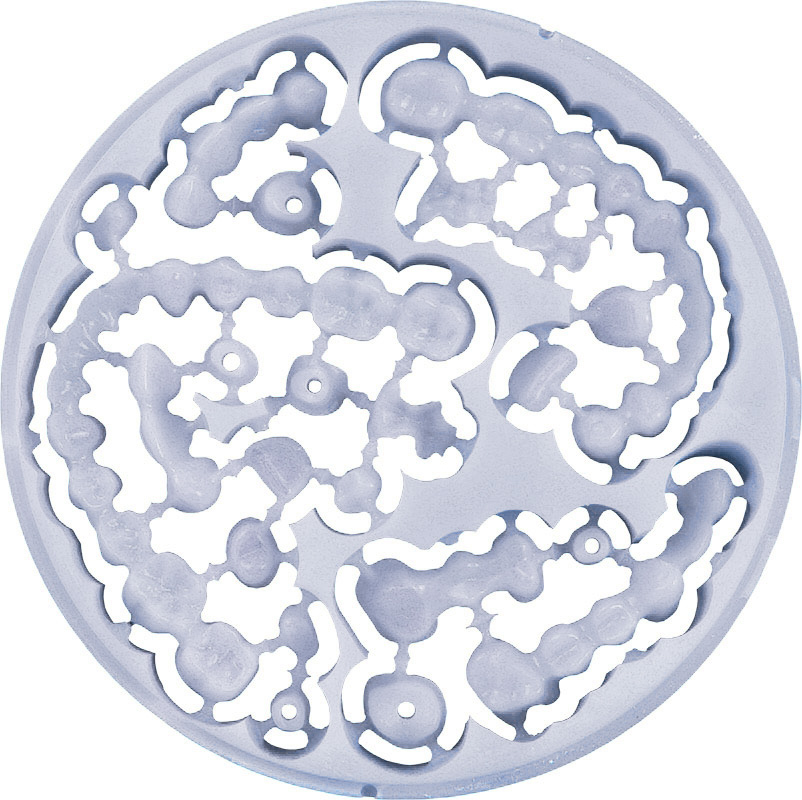

Bite splints

Bite splints are removable dental appliances molded to fit the upper or lower arches of teeth. People prone to nighttime clenching or gnashing can wear bite splints at night to prevent damaging their teeth.